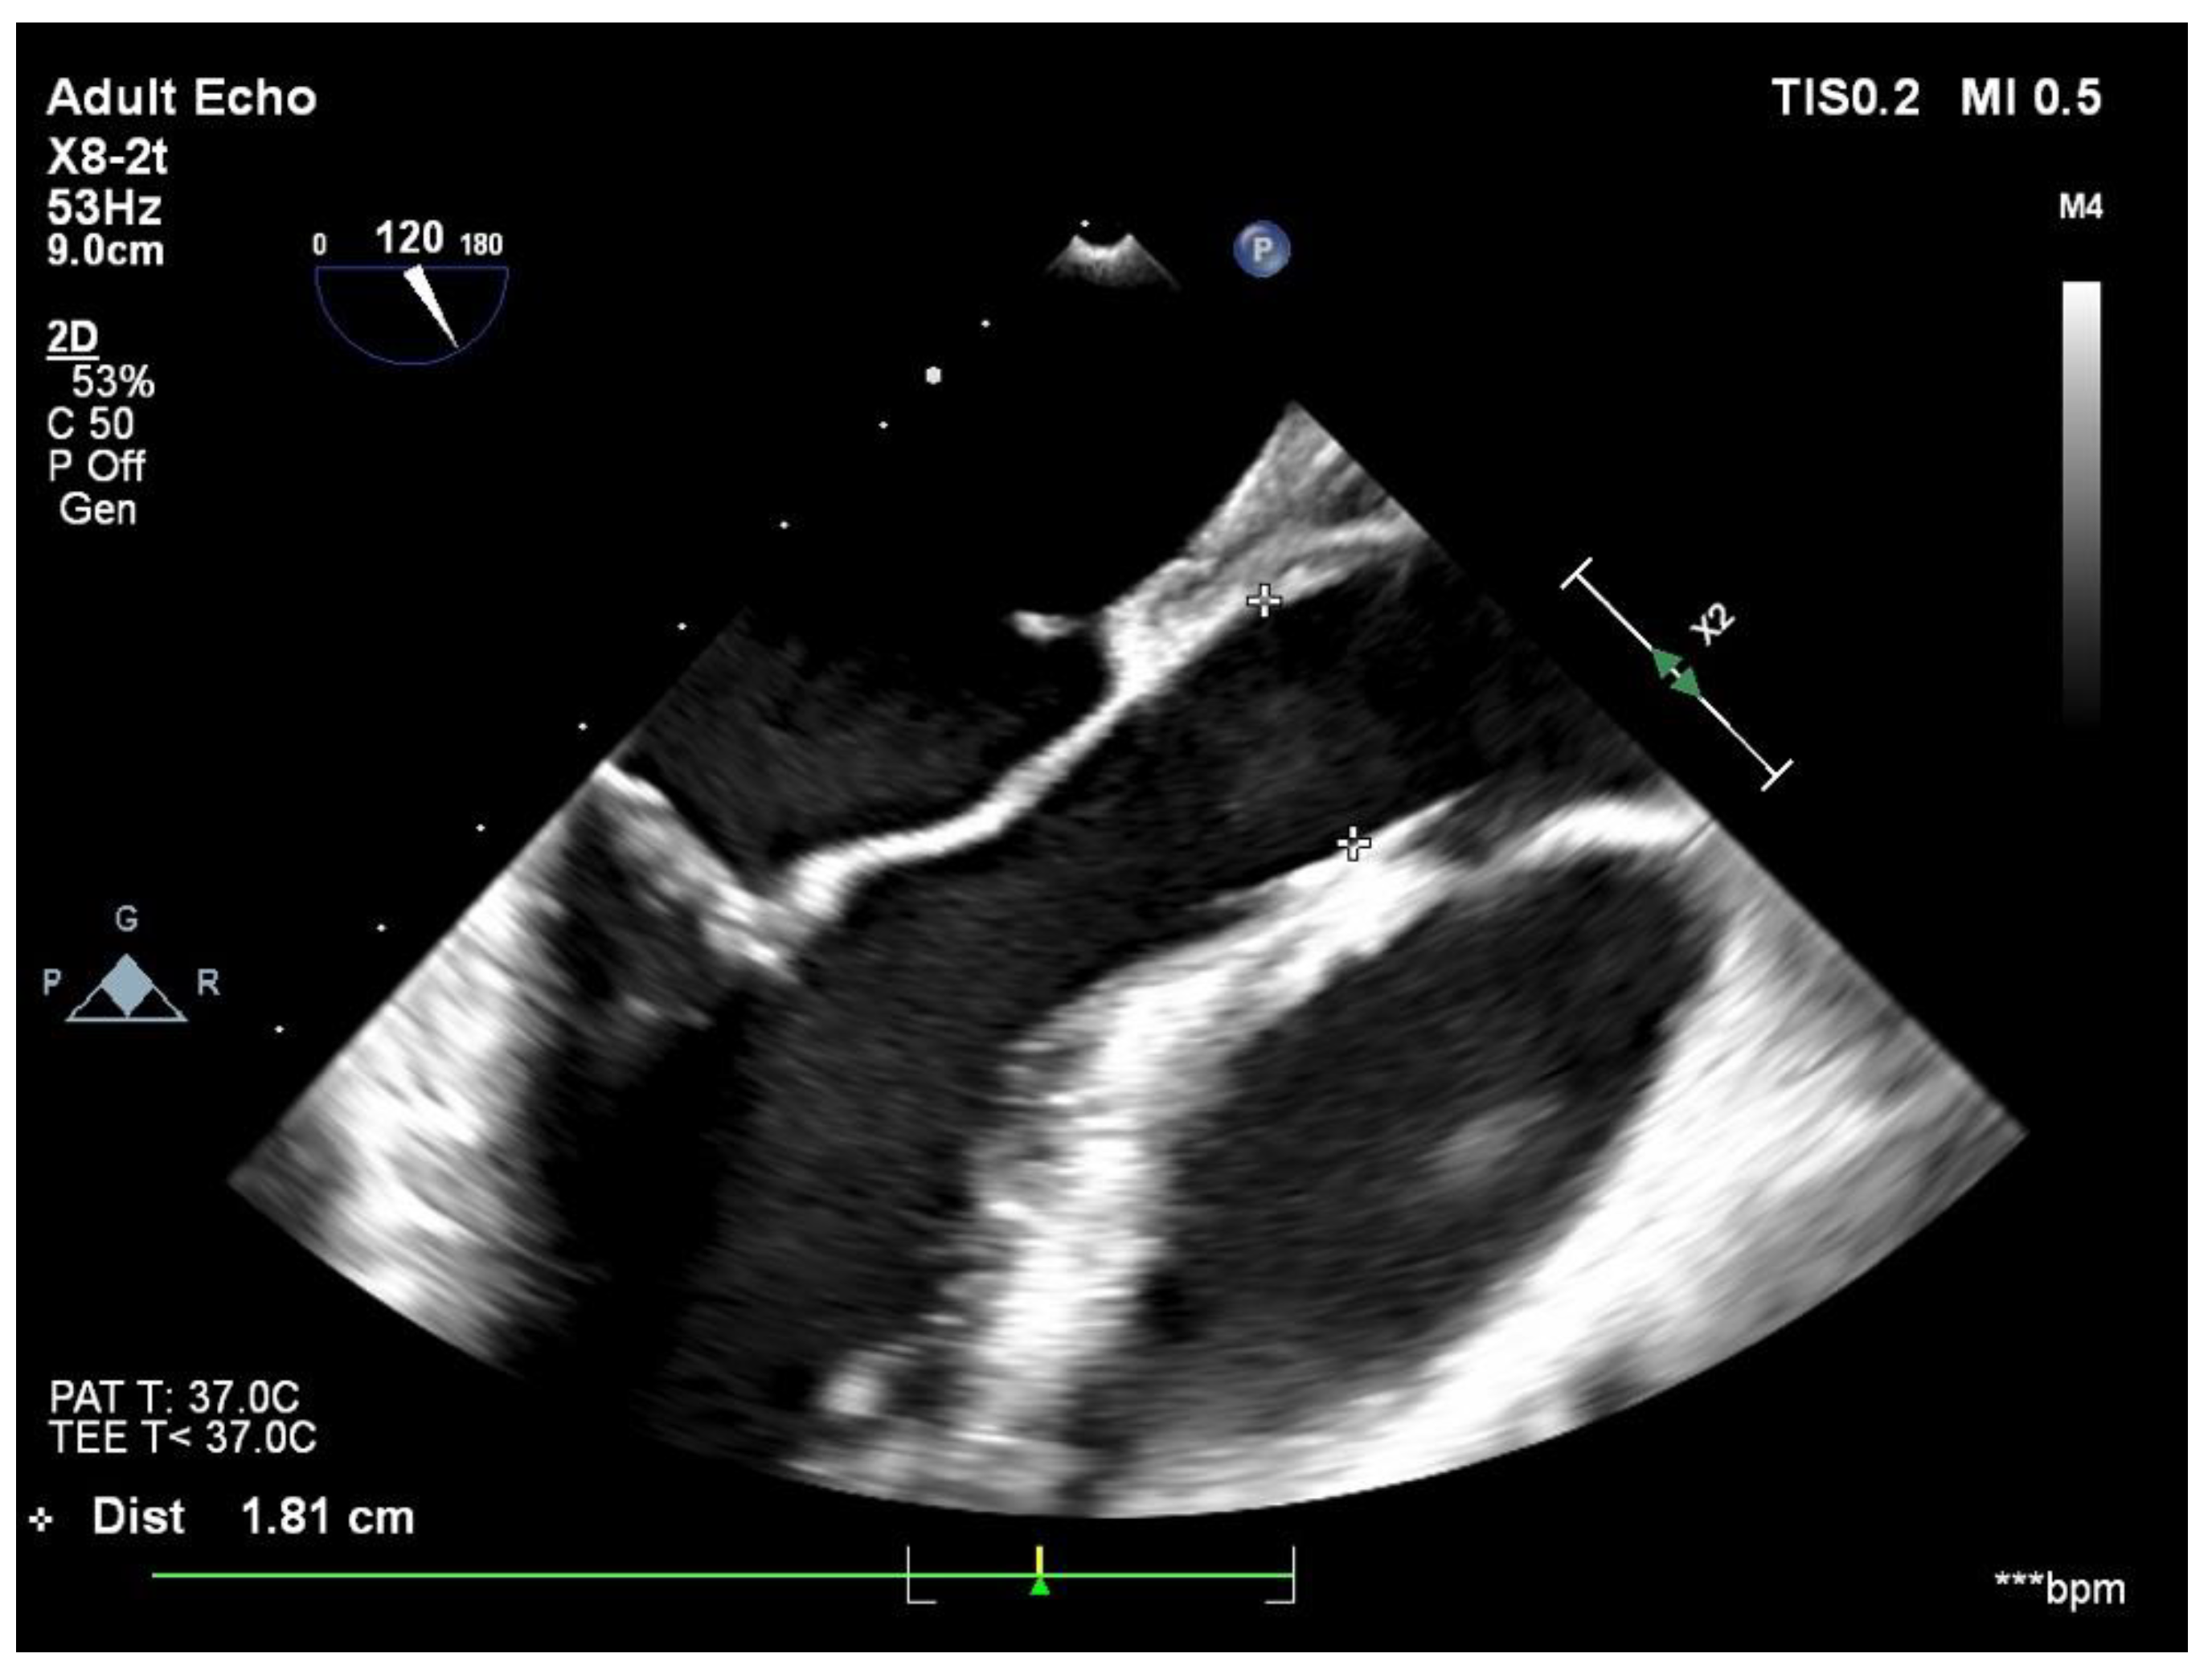

2. Case Report